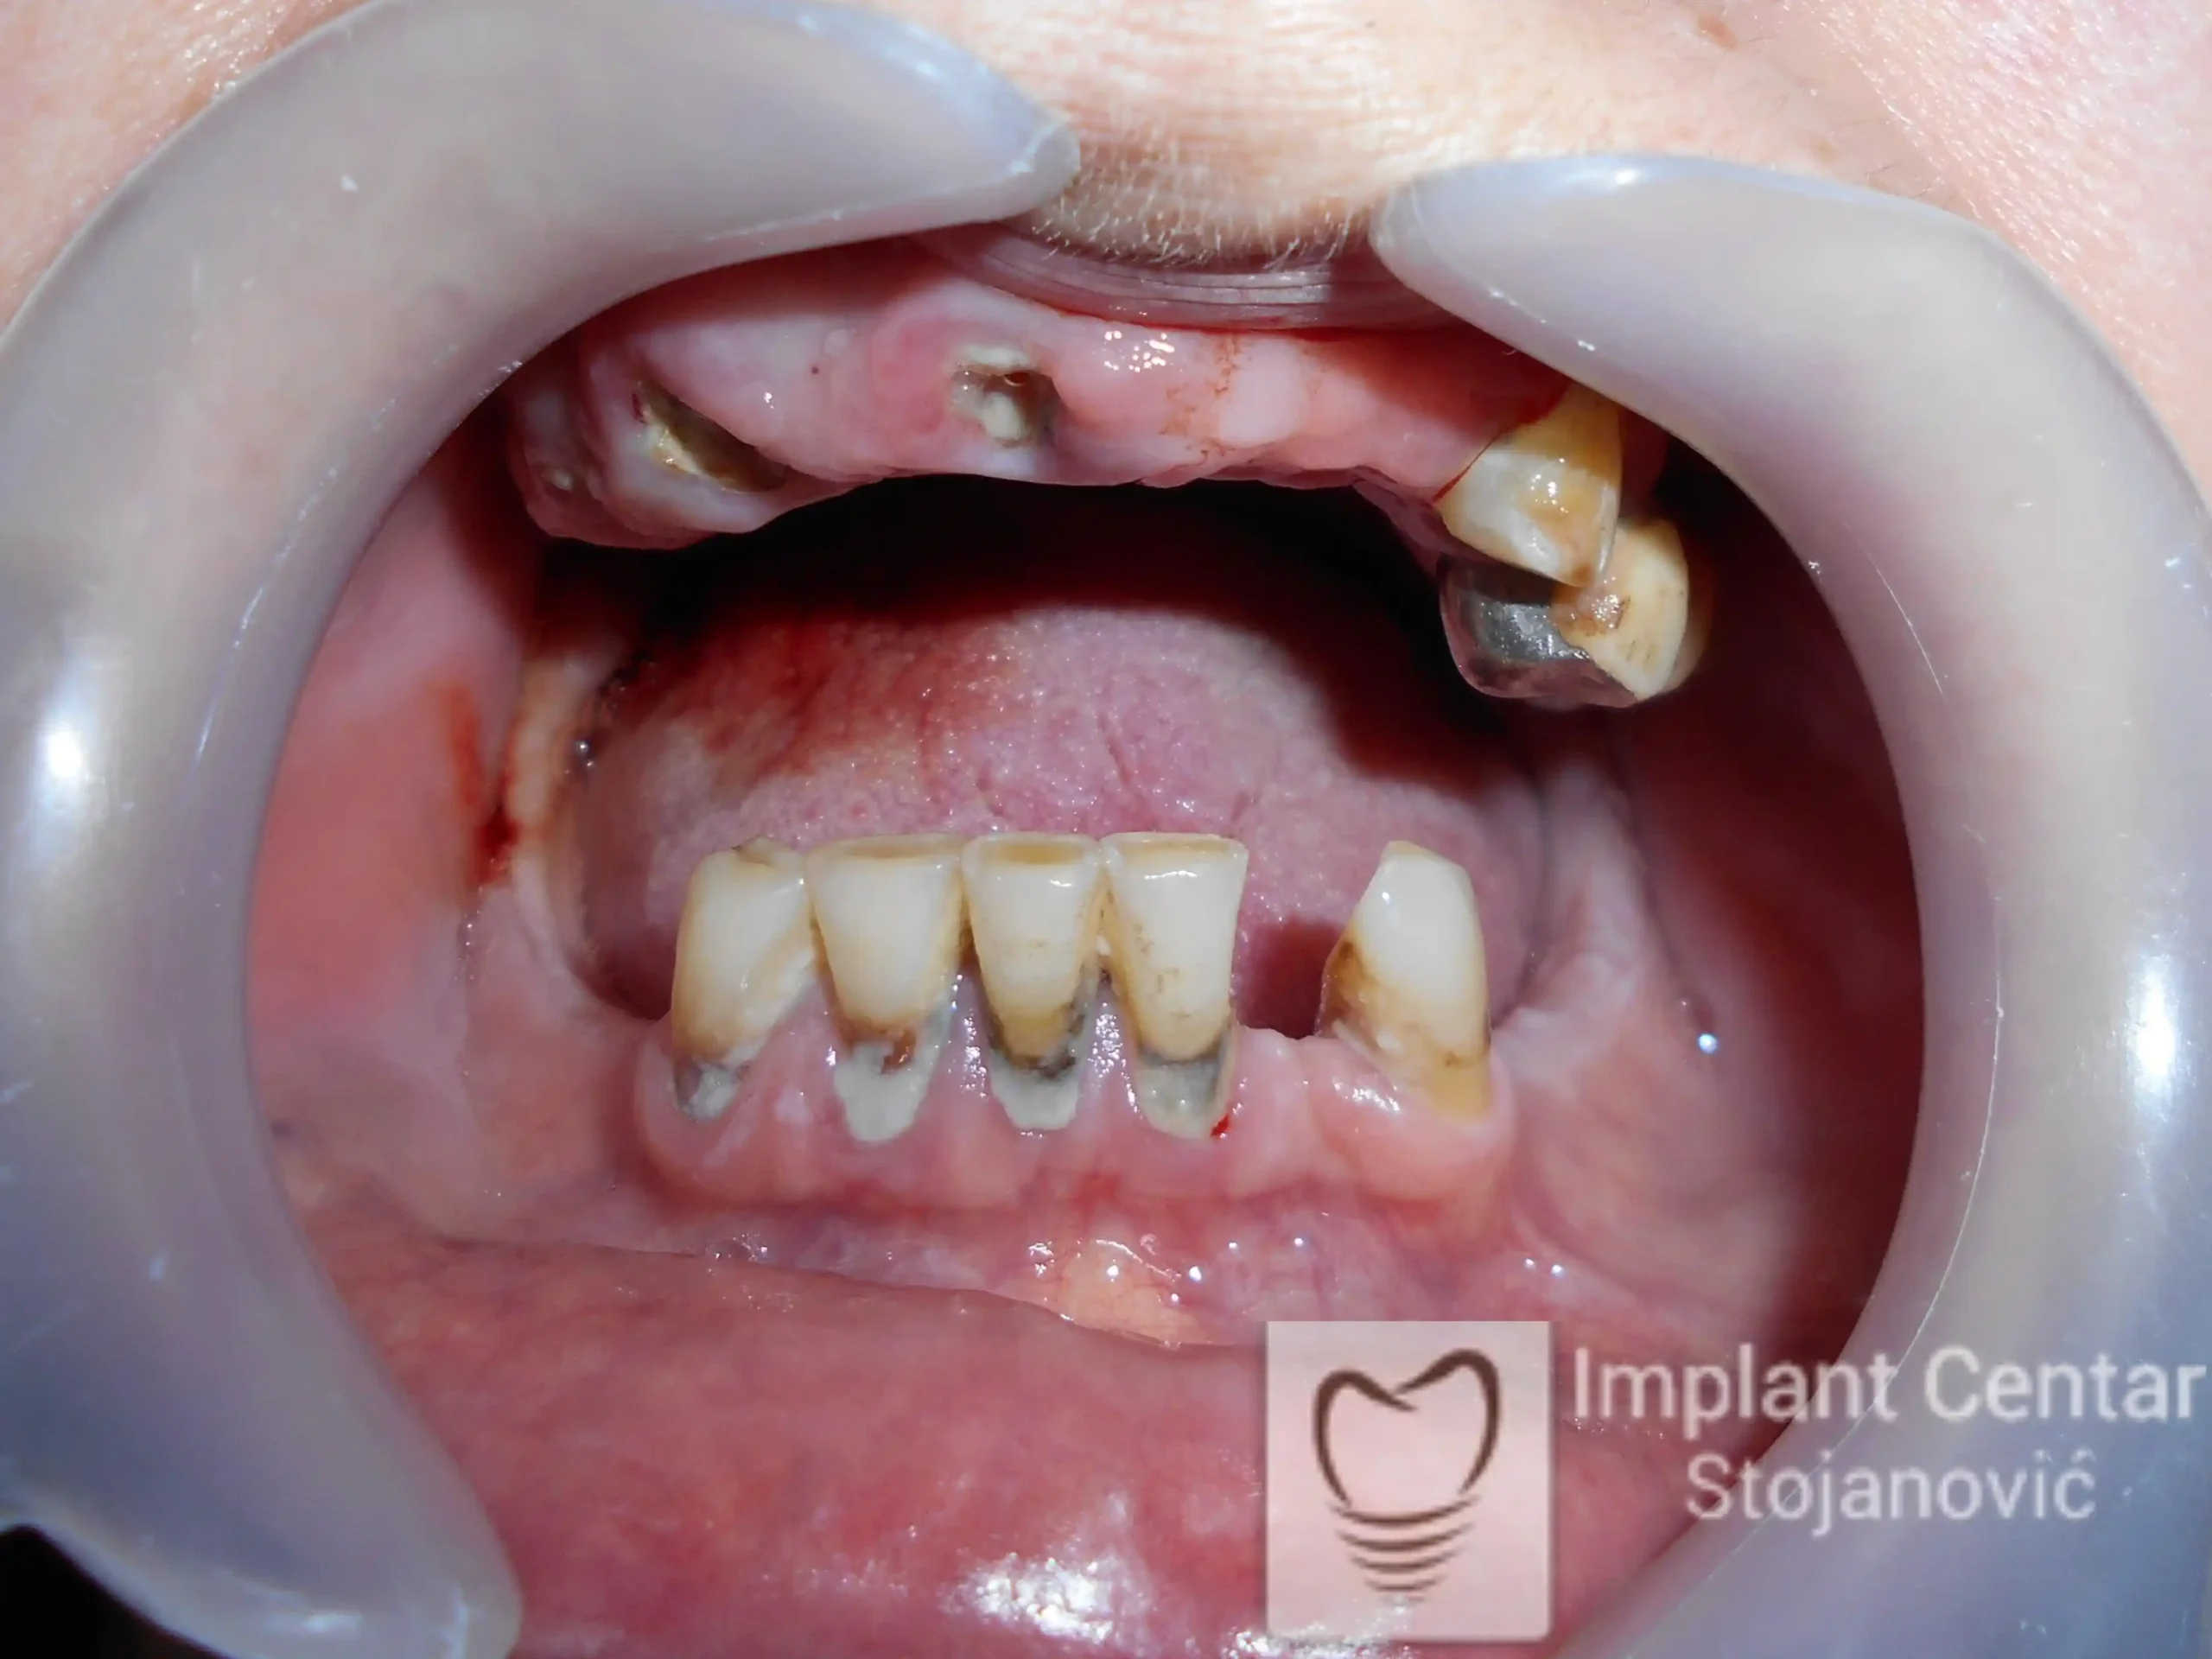

Na slikama 1 i 2 prikazan je klinički izgled pacijenta pre početka terapije. Nakon detaljnog kliničkog pregleda, analize radioloških snimaka, kao i razgovora sa pacijentom o njegovim željama i očekivanjima, izrađen je sveobuhvatan plan terapije. Terapija je podrazumevala vađenje preostalih zuba, ugradnju dentalnih implantata i izradu fiksnog protetskog rada na implantatima.

Tokom perioda osteointegracije, pacijent je bio zbrinut fiksnim privremenim krunicama na implantatima, čime su očuvani estetika i funkcija. Nakon završetka perioda integracije, izrađeni su definitivni cirkonijum-keramički mostovi (slika 6 i 7 ).

Pacijent je izuzetno zadovoljan postignutim rezultatom, jer su u potpunosti vraćeni prirodan izgled osmeha i puna oralna funkcija.